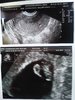

dawno mnie tu nie było ale trochę ponadrabiałam. Chwale się moim przystojniakiem, już widziałam to małe serducho!! coś pięknego! termin się skrócił o 1 dzień (3.09) :D Ale następnym razem zobacze je za miesiąc ;( ;(..... no ale odpalam jakiś serialik i pewnie zleci :D

@AniaBaniaProszekDoPrania u lala...pieknie:p ale urusl ten pęcherzyk hehe